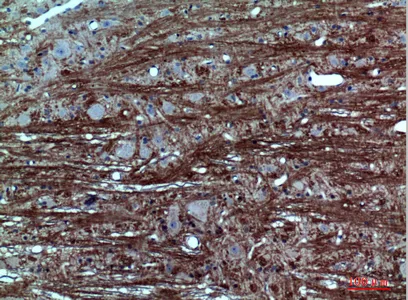

Catenin-β Rabbit Polyclonal Antibody

Cat: APRab08004

Size1:50μl Price1:$118

Size2:100μl Price2:$220

Size3:500μl Price3:$980

Size2:100μl Price2:$220

Size3:500μl Price3:$980